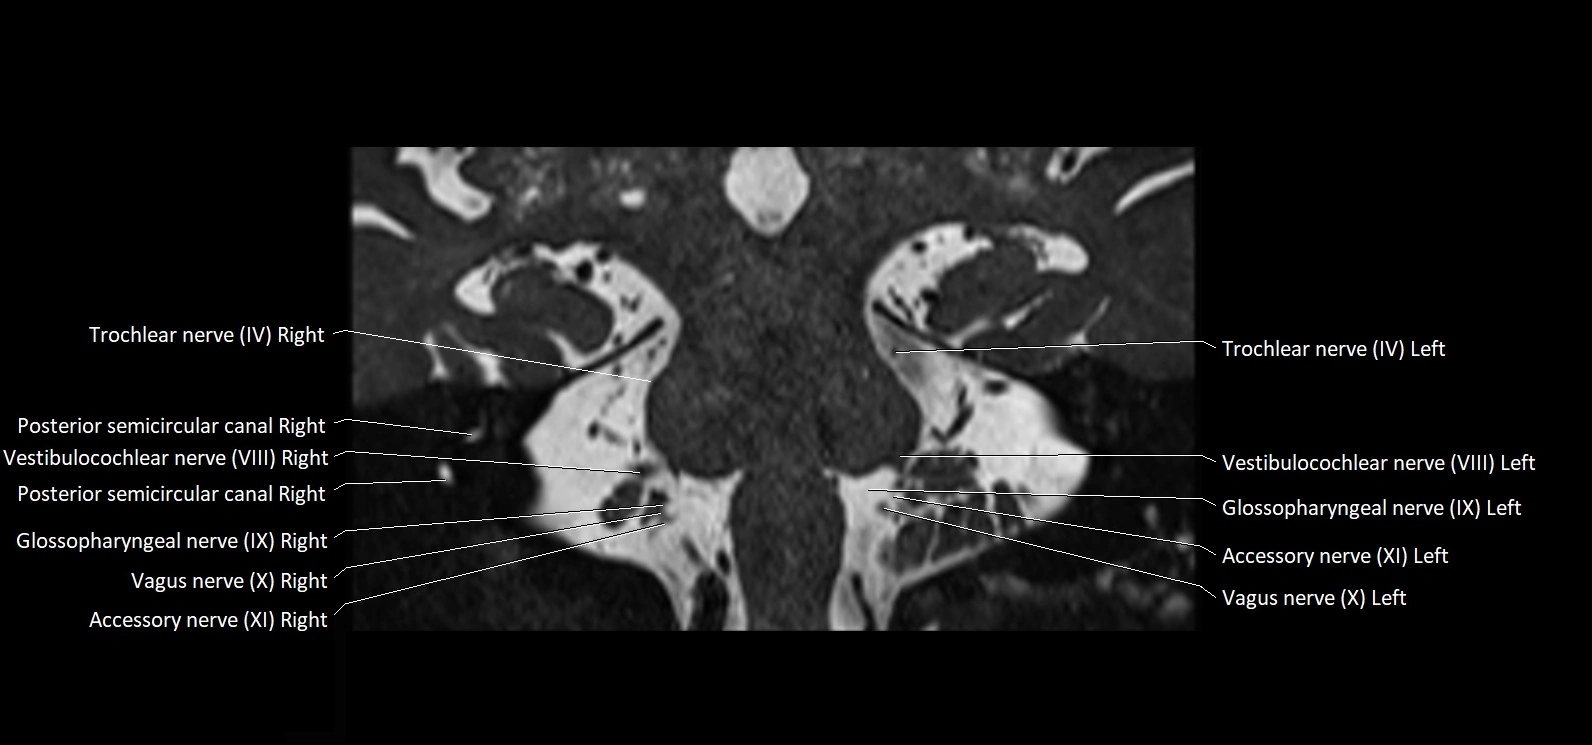

MRI Appearance

• The abducens nerve is a small, thin, linear structure

• Best visualized on high-resolution T2-weighted 3D MRI sequences (e.g., FIESTA or CISS)

• Seen as a hypointense (dark) line running from the brainstem at the pontomedullary junction, traversing the prepontine cistern, and entering Dorello’s canal under the petrosphenoidal ligament, then into the cavernous sinus, and finally the orbit

• May be challenging to visualize in standard MRI due to its small size

• Pathology may be inferred by absence, displacement, or enhancement of the nerve

MRI images

image